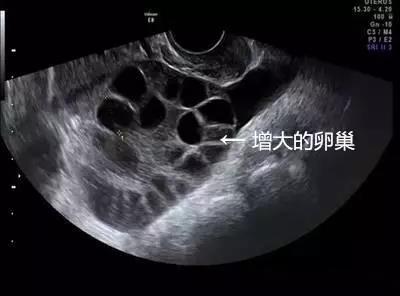

取卵成功后,中介就没有再联系琳琳。但取卵5天后,琳琳出现持续性下腹胀,还有十分明显的胸闷症状。她再次联系卖卵中介,但对方拒绝承担责任,还威胁琳琳不要再纠缠。琳琳到这家妇幼保健院就诊,B超提示腹腔内大量积液,胸腔少量积液,卵巢增大超过3倍以上,考虑是卵巢过度刺激综合症,被收治住院。

由于腹腔内积液增多,肚子大了一圈,琳琳无法平躺,入眠困难,进食困难,非常痛苦。在先后进行2次腹腔穿刺抽出腹水后,症状才得以缓解,最后住院10天左右才得以出院。